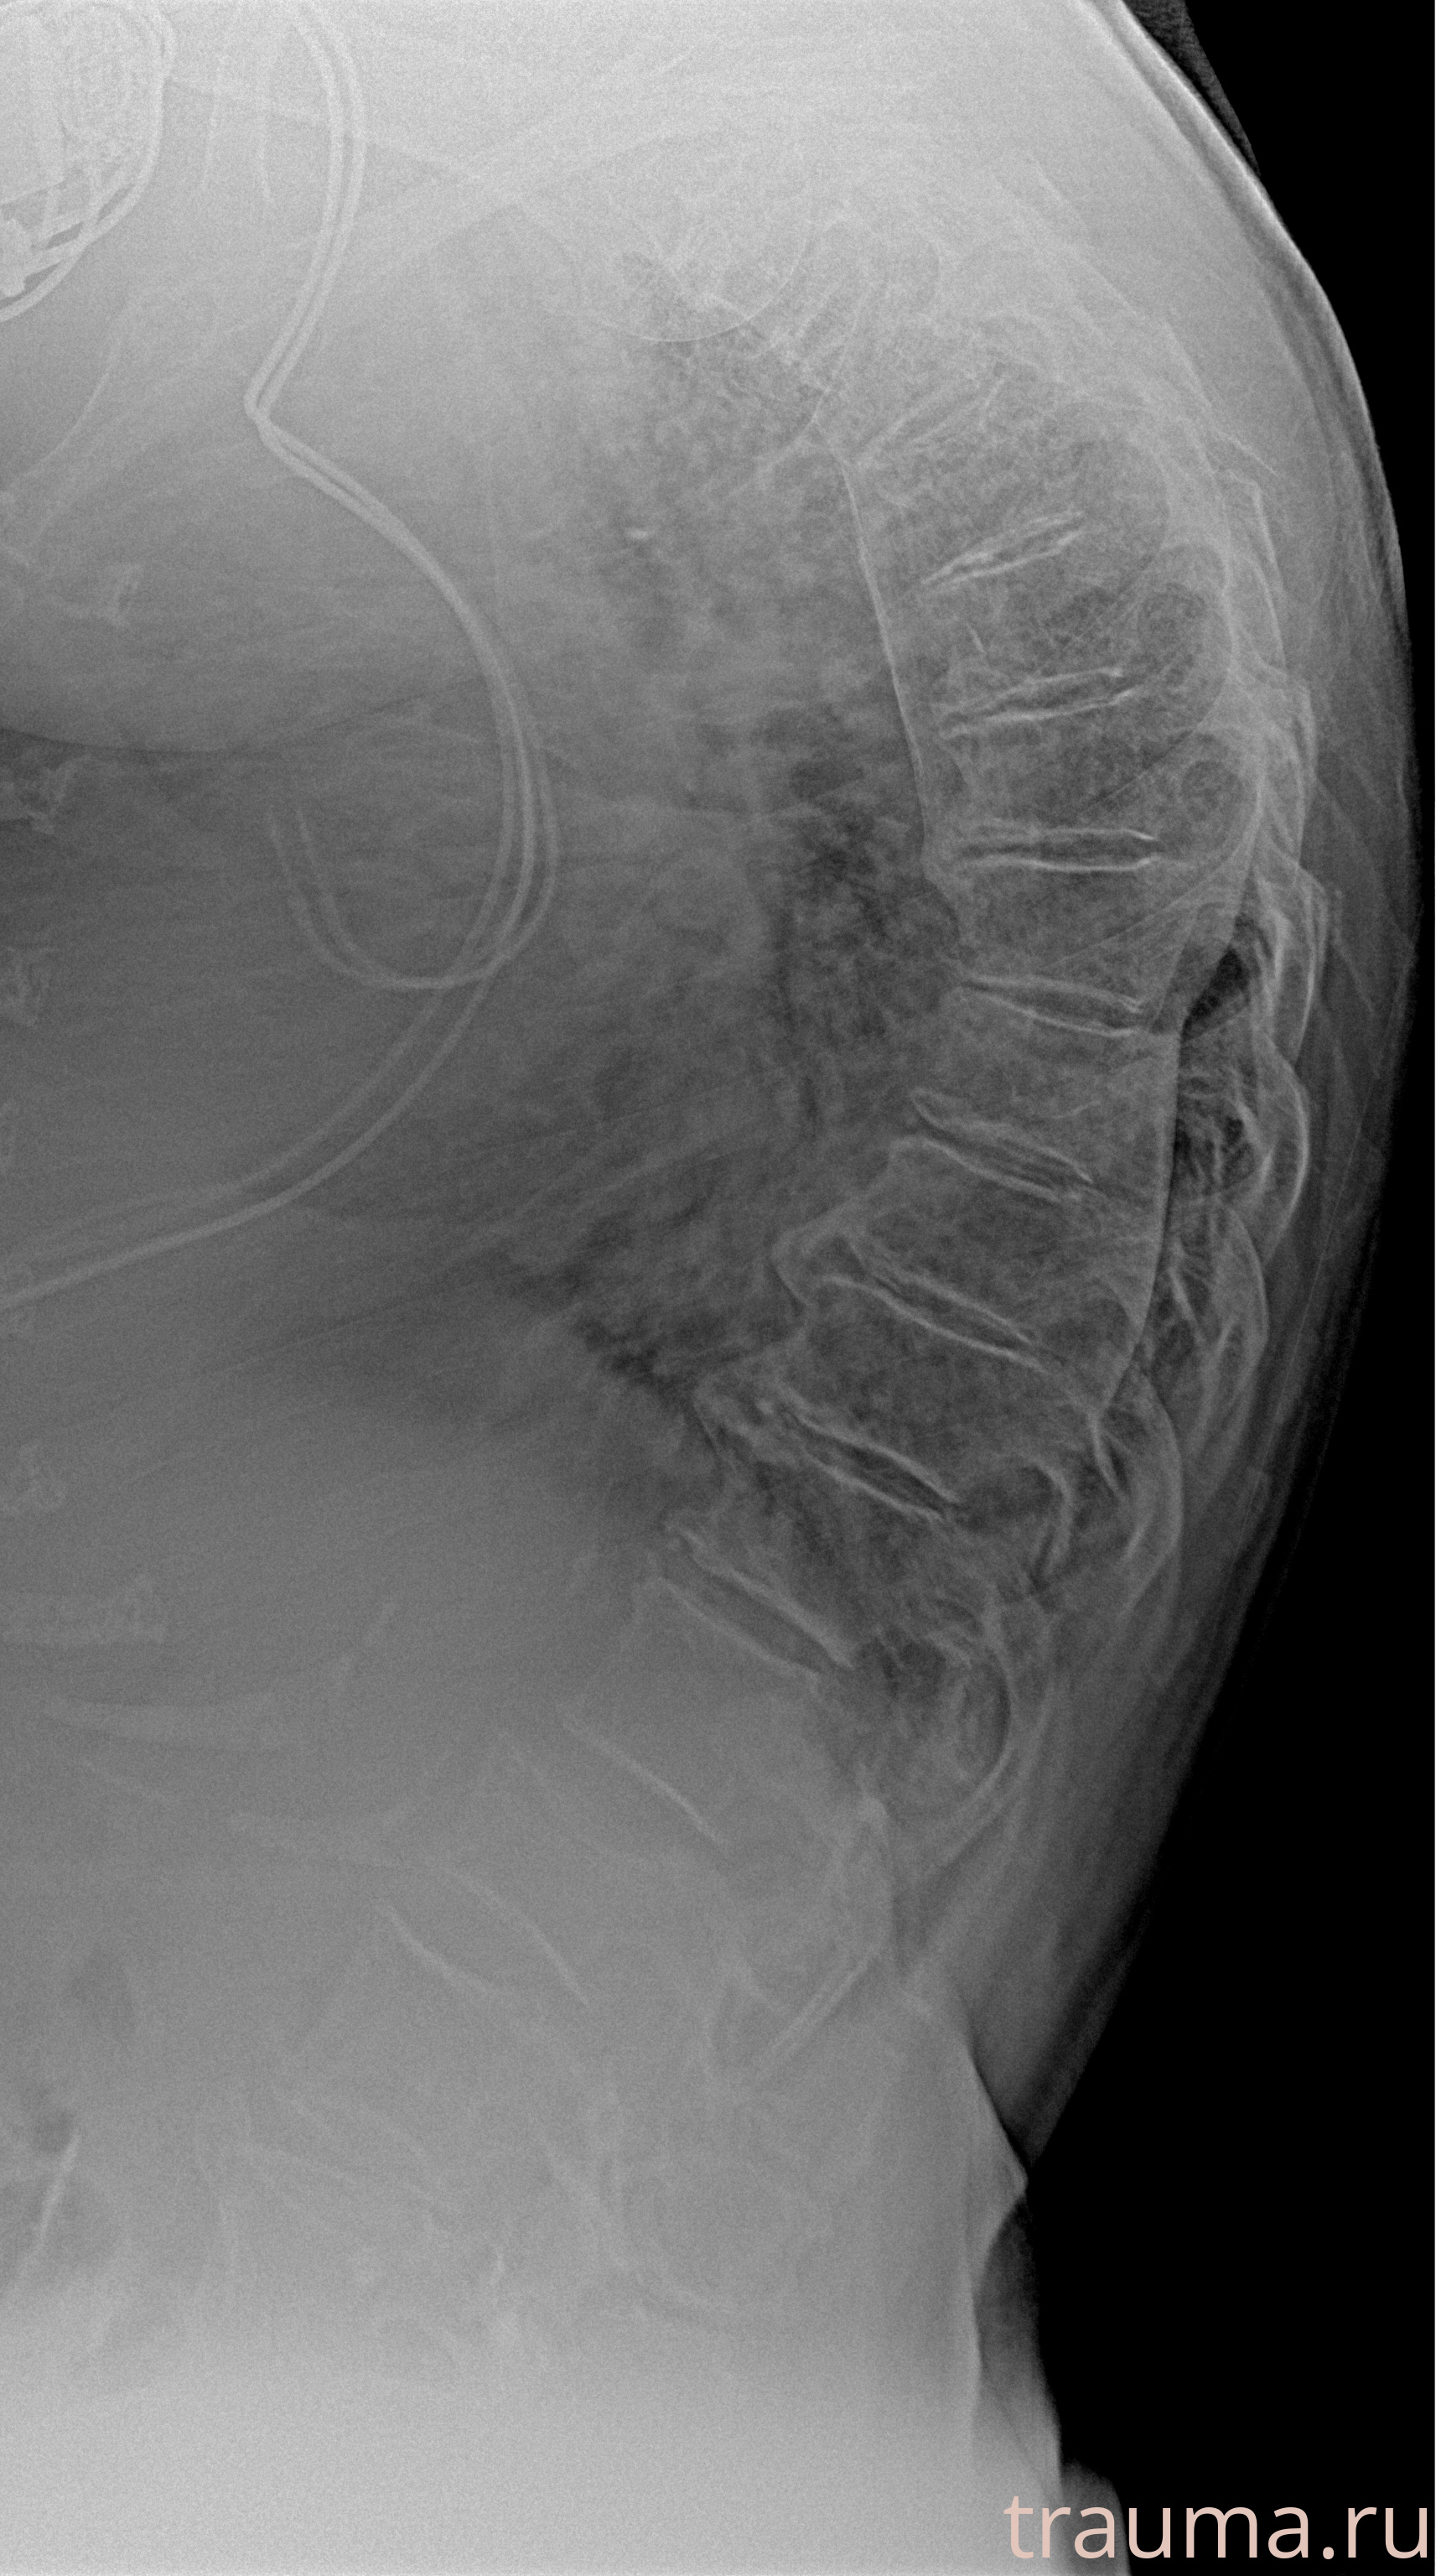

Рентген на дому: по вашему адресу приезжает врач-рентгенолог, травматолог-ортопед с мобильным рентгеновским аппаратом, проводит диагностику травмы или заболевания, делает необходимые рентгенограммы, дает рекомендации по дальнейшему лечению. Получить качественные снимки в домашних условиях возможно благодаря уникальной методике, разработанной МосРентген Центром для института  Склифосовского